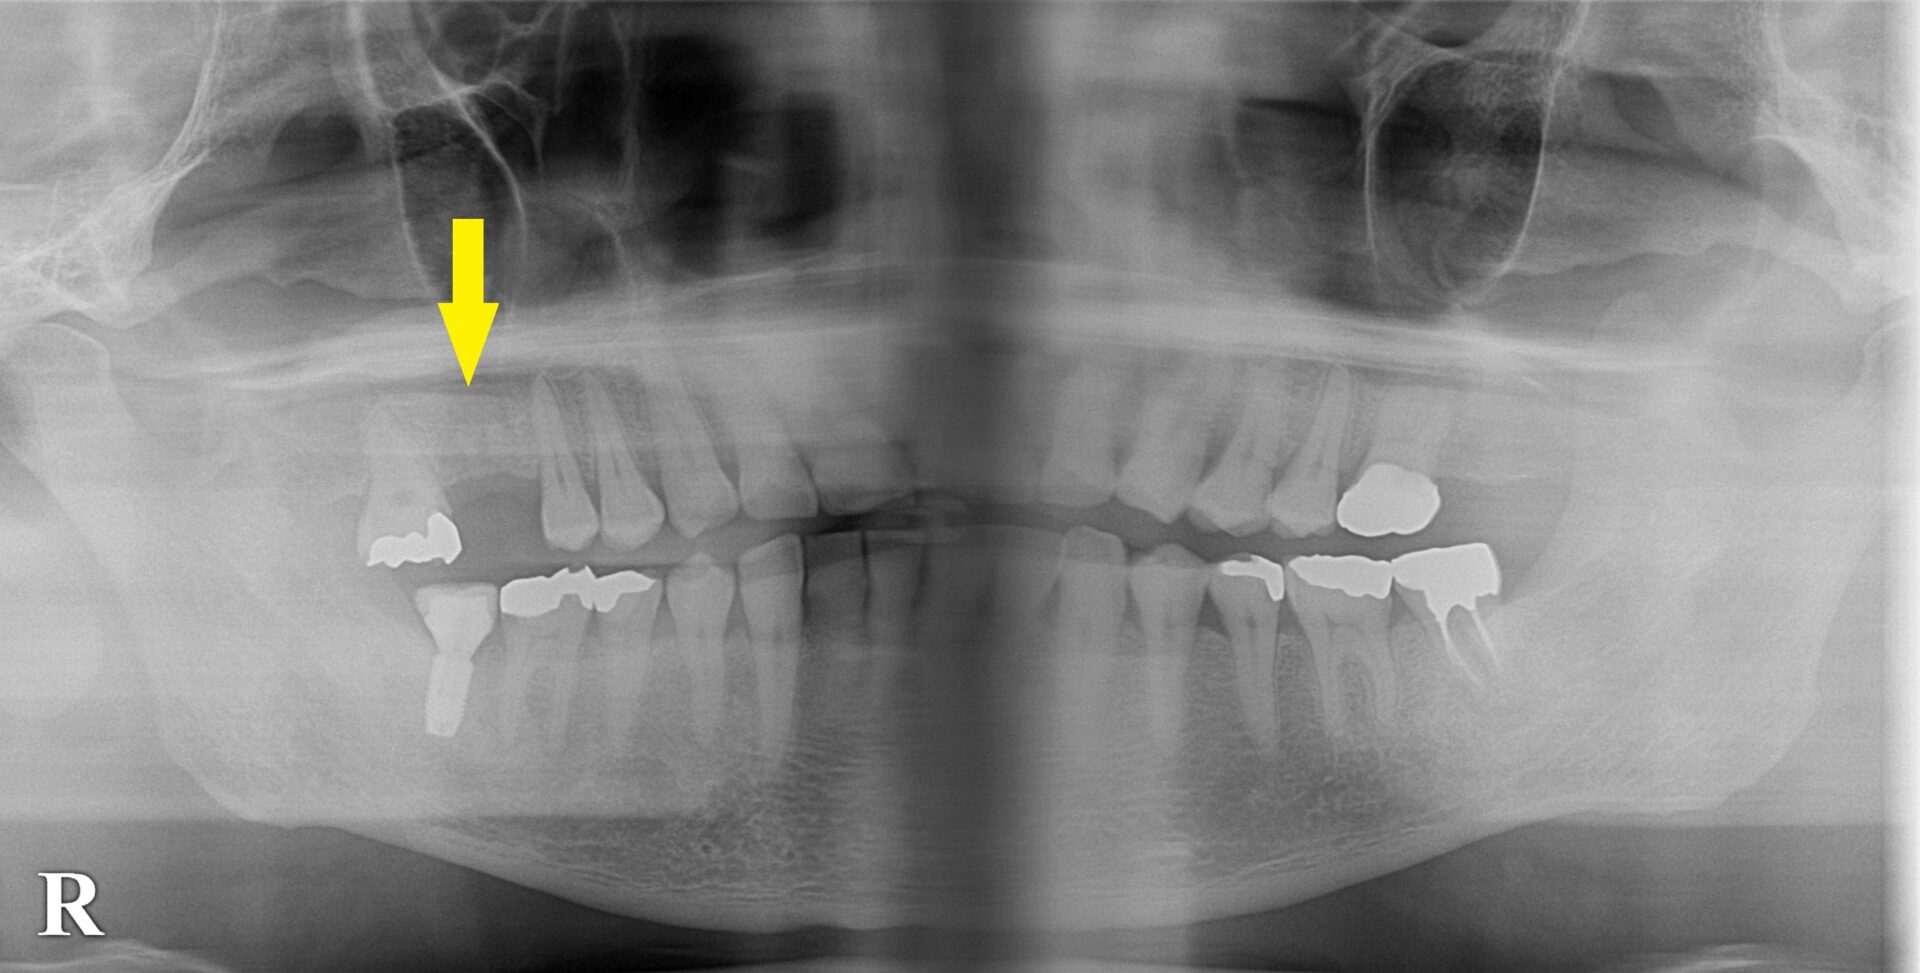

以前に右下顎の第二大臼歯にインプラント治療をされた患者様ですが、今回、右上顎第一大臼歯が抜歯となり、インプラント治療を希望されて来院されました。

骨の状態を詳しく調べるために、CTを撮影してみると、骨の幅は十分ですが、高さが4~5mmと少なめでした(下の写真、2段目)。